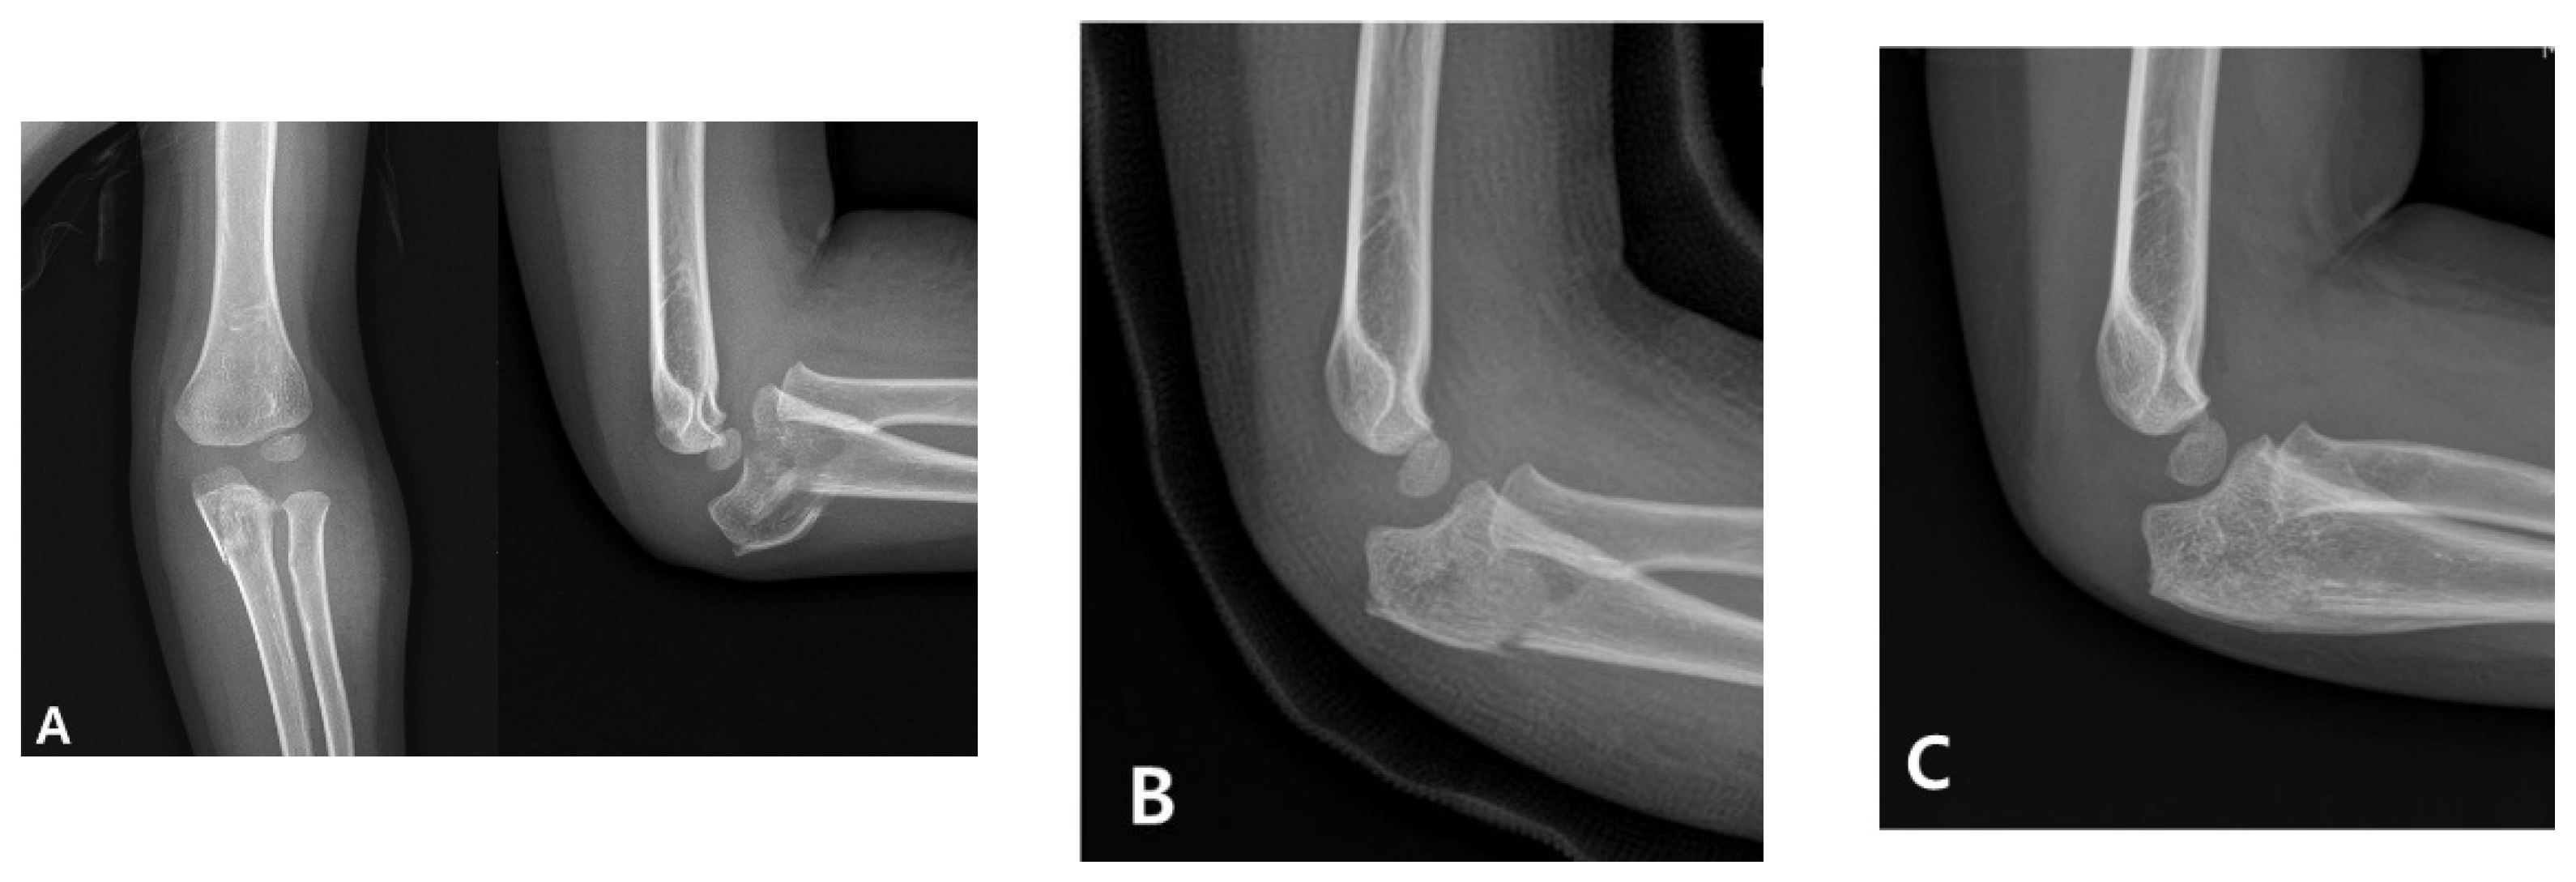

Management in children initially involves the urgent anatomical realignment of the ulna and a reduction in the radial head. This is most commonly achieved through closed reduction and casting as a first-line conservative approach. If successful, this method stabilizes the radiocapitellar joint and restores elbow function without requiring surgical intervention (Figure 1) [4]. However, in cases in which the alignment is unstable or cannot be maintained, surgical stabilization using techniques such as intramedullary nailing or plating is indicated [5,6]. Therefore, a prompt and accurate diagnosis is critical for determining the appropriate treatment pathway and avoiding long-term complications, such as persistent radial head dislocation, limited motion, and elbow deformity.

Figure 1. Radiographic progression of an acute pediatric Monteggia fracture treated conservatively. (A) Initial anteroposterior and lateral elbow radiographs of a 3-year-old boy revealing anterior dislocation of the radial head with a fracture of the proximal ulna, consistent with a Bado type I Monteggia fracture. (B) Closed reduction and casting were performed promptly. Post-reduction images confirmed the anatomical realignment of both the ulna and radial head. (C) Follow-up radiographs obtained 2 months after the injury demonstrate maintained reduction and progressive healing without the need for surgical intervention.